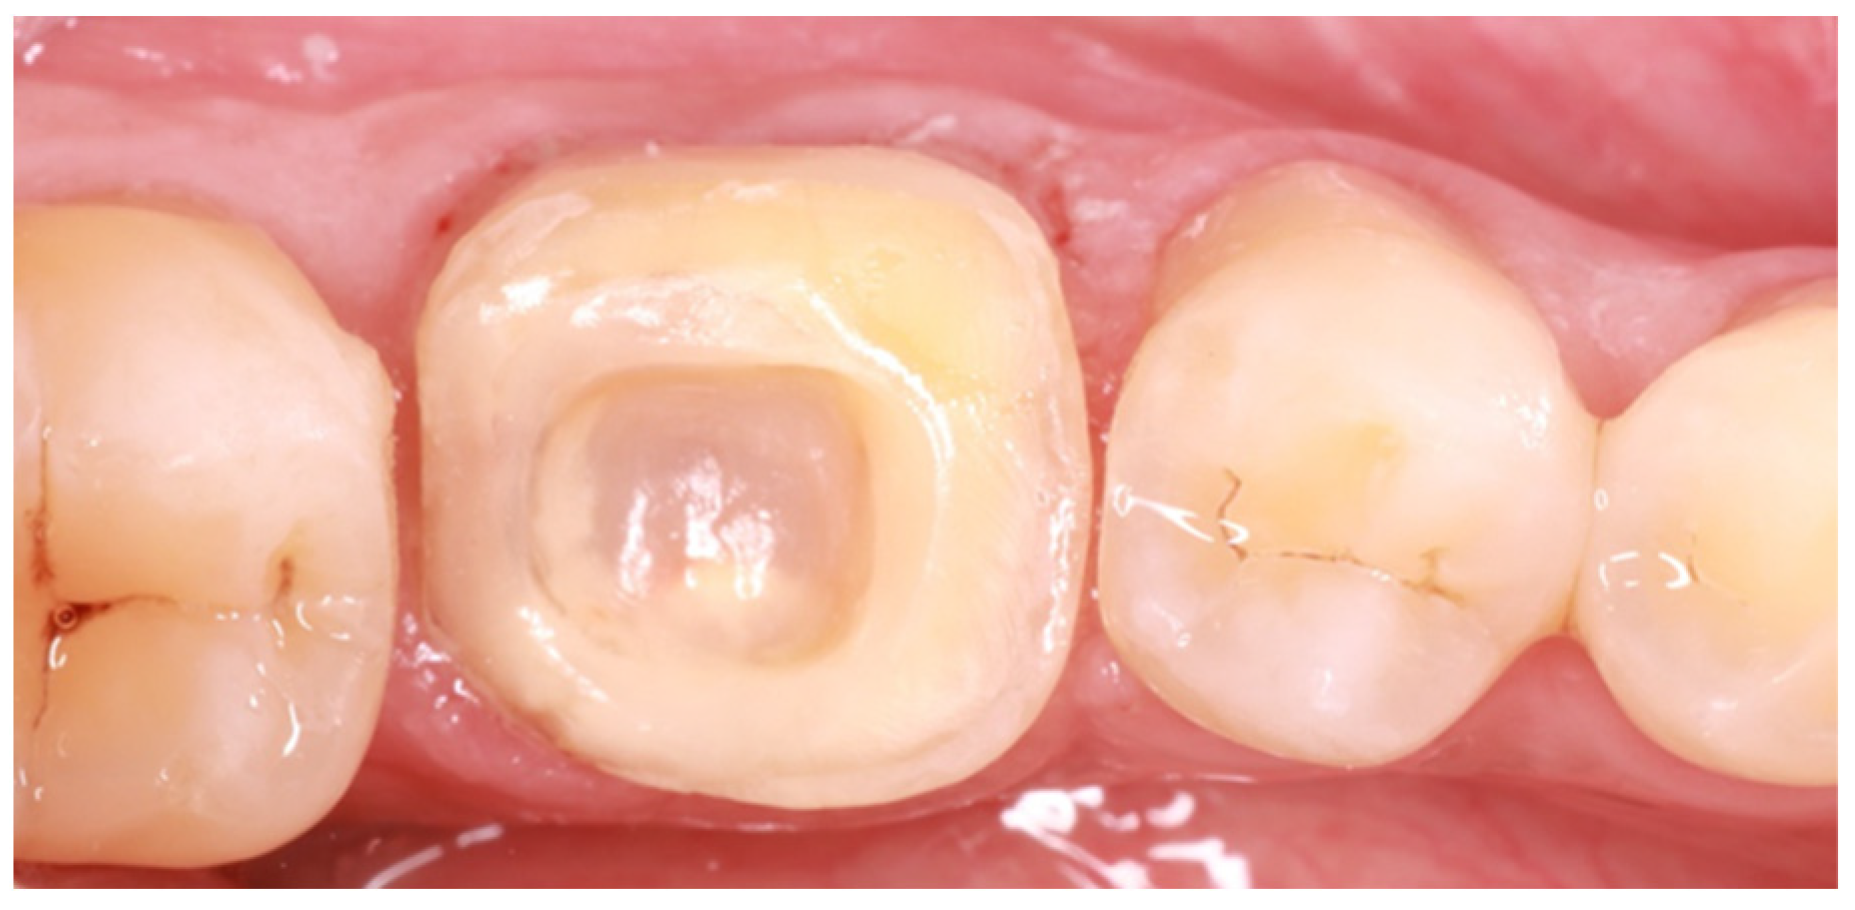

First, existing restorations and decayed tissue were removed. Given that the tooth was restorable, a provisional restoration was placed in order to prevent microleakage and the patient was referred for an endodontic reintervention as the existing root canal treatment was not satisfactory. Enamel presence at a percentage higher than 80% of the tooth circumference substantiated the choice of an endocrown restoration (Figure 2). This type of prosthesis demands the presence of healthy enamel for the adhesive procedures to be more effective [10]. This condition is so crucial that many reports have placed a lack of cervical enamel among the contraindications for endocrown restorations [11].

Figure 2. Adequate enamel presence after removal of previous restorations.